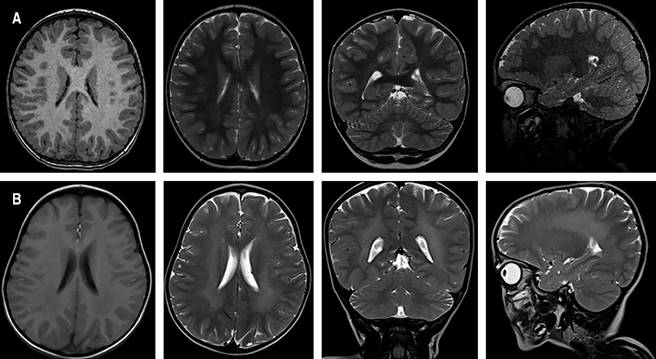

En una RMC realizada siete meses después de la primera, se observó alteración de la intensidad de la señal en la sustancia blanca con hiperintensidad en T2 e hipointensidad en T1 (Figura 1), sugestivas de desmielinización. Aunque fue considerada como una variante de LDM de inicio infantil tardío, su comportamiento clínico no cumplió con los criterios recomendados para trasplante de médula ósea, por lo cual solo recibió cuidados paliativos y terapia de rehabilitación.

Figura 1: A) Cortes axiales en T1, FLAIR; corte sagital y axial en T2 en la primera resonancia magnética. B) Imágenes de resonancia después de siete meses que evidencia alteración de la intensidad de la señal en la sustancia blanca, con hiperintensidad en T2 e hipointensidad en T1.